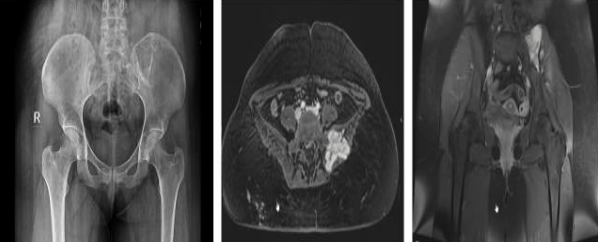

Figure 7,8,9,10, 11, 12

Case 3 - 35 year old male who presented with low back ache since 5 years and swelling since 2 year. Upon evaluation with X-ray of pelvis was found to have a lytic lesion in the left ileum on posterior aspect Fig-7. On MRI T2 hyper-intense lesion was found the posterior ileum with soft tissue component and cortical breech on posterior aspect measuring 5.7x 4.1x 7.3cm Fig-8.. Patient underwent extended curettage of the lesion and reconstruction with Poly-methyl methacrylate cement and Post-op Histopathology showed oval to spindle shaped cells with indistinct cell borders, round to oval hyperchromatic nucleus and moderate amount of cytoplasm- fibromatosis Fig-9. Upon follow up for 3 years patient is disease free.

Case 4- 21 year old female patient who presented with pain and swelling of the left lower back area since 8 months. Upon clinic radiological evaluation – on x ray was found to have a lytic lesion in the left postero-superior iliac wing and MRI showed T2 intermediate to hyper-intense lesion on the left iliac wing with cortical breech and extra-osseous soft tissue component involving the iliacus muscle anteriorly and gluteus medius posteriorly measuring 5.9x5.6x6.3 cm with T2 hypointense rim around the lesion Fig-10. Histopathology proved to be fibromatosis and after multidisciplinary team meeting patient was planned for extended curettage and reconstruction Fig-11. Reconstruction was done using poly-methyl methacrylate cement and two K-wire for stabilisation with post-op Histopathology confirming the diagnosis Fig-12. Upon one year of follow up patient does not have any complaints and doing well.